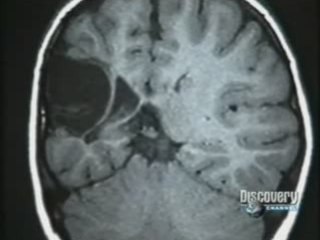

Scientific American se hace eco de la salida al mercado de un dispositivo que permite a los ciegos tener cierta conciencia de su entorno visual. El producto consiste en una “piruleta” con 20×20 electrodos que se coloca sobre la lengua. El dispositivo se basa en una primera demostración de la idea hecha en 2003 por Wicab, una compañía de Middleton (EEUU). El sistema se llama BrainPort y trata, en la medida de lo posible, suplir la información visual que los dos millones de nervios ópticos transmiten al cerebro. Nuestros ojos no ven, en realidad envían la información al cerebro y éste la interpreta en forma de imágenes. Si los ojos o los nervios están dañados entonces no llega tal información y el cerebro no puede elaborar imágenes. Por eso se pensó en el pasado en el implante de electrodos directamente en la región visual del cerebro (córtex visual) de los invidentes, pero esta técnica es muy invasiva.